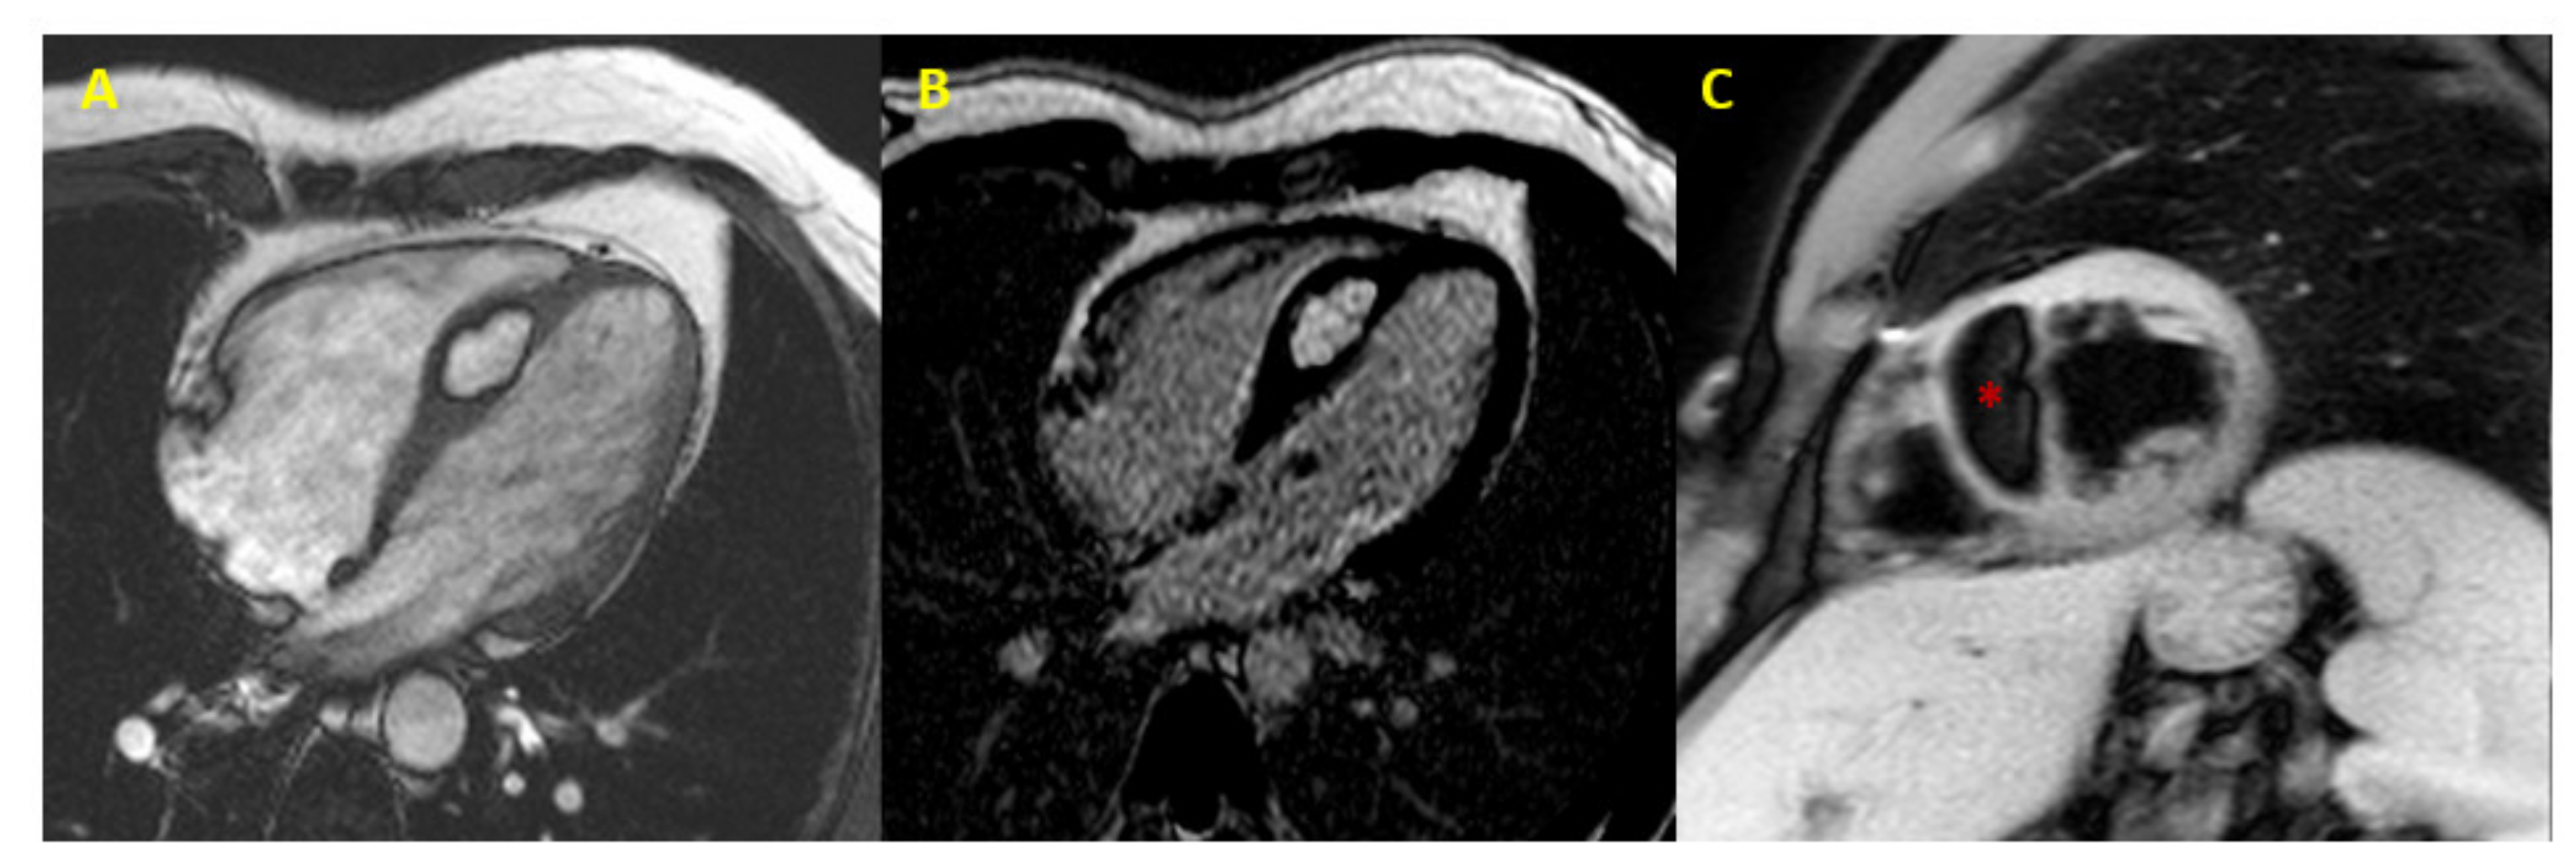

Figure 3.

Cardiac lipoma at CMR. CMR image (4-chamber view) showing septal hypertrophy characterized by hyperintense signal in SSFP and LGE sequences (Panel (A,B)), and signal suppression (* asterisk in Panel (C)) in fat-saturated images (CMR = cardiac magnetic resonance; SSFP = steady-state free precession; LGE = late gadolinium enhancement).